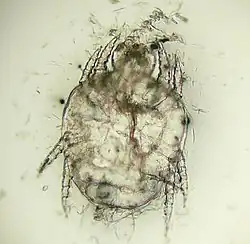

"Cheyletiella yasguri" (?) from a dog

Cheyletiella yasguri (?) from a dog

The adult mites are about 0.385 millimeters long, have eight legs with combs instead of claws, and have palpi that end in prominent hooks.[5] They do not burrow into the skin, but live in the keratin level. Their entire 21-day life cycle is on one host. They cannot survive off the host for more than 10 days.[6]